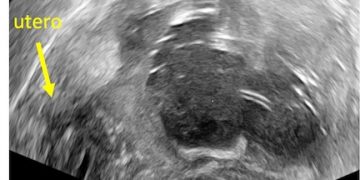

Cari soci, finalmente online le soluzioni dei casi di Maggio!!! Caso 1 Scarica il File Caso 2 [pdf-embedder url="https://www.sieog.it/wp-content/uploads/2022/05/caso-clinico-maggio-2-risposta.pdf" title="caso...